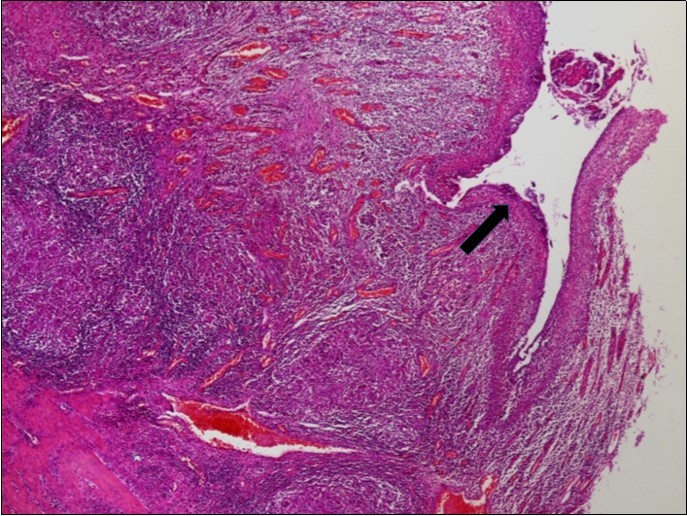

The histopathologic examination of the resected bowel specimen showedcaseating granulomatous inflammation (Figure 2), consistent with intestinal small bowel tuberculosis complicated with peritonitis and perforation (Figure 3).

Figure 3.Signs of acute peritonitis in the intestinal mucosa